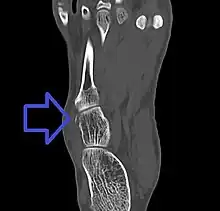

| Avulsion fracture of the right cuboid bone of the foot | |

A cuboid fracture is a fracture of the cuboid bone of the foot. Diagnosis is by X-ray imaging, magnetic resonance imaging, or bone scan.[1] Treatment may be conservative or involve surgery, depending on the type of fracture.[1] They are rare.[1]